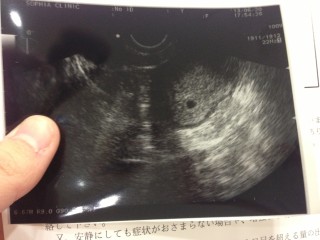

4週4日で受診し、何も見えず、早いですが待ちきれずまた産婦人科へ。5週にしてようやく会えました。ぼやっと写った赤ちゃんの袋をみたときの感動は忘れられません!成長が楽しみです!

ちっちゃーい。

けどむっちゃ可愛い(*^_^*)

これから頑張ります☆